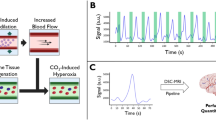

Bottom: BOLD-functional MRI activation paradigm: 5 repetitive cycles including BN time (yellow) and BH time (red). The 5 cycles of 69 s (23 measurements) each were followed by 60 s (20 measurements) of regular breathing. Top: detailed view: one cycle consists of the instructions “breathe normally,” “breathe in” (i), “breathe out” (o), and “do not breathe”

All further processing of the data was performed using a script programmed in MATLAB (R2018b (The MathWorks, Inc., Natick, Massachusetts; http://www.mathworks.com)). Four templates (territories of anterior cerebral artery (ACA), middle cerebral artery (MCA), posterior cerebral artery (PCA), and cerebellar vascular territories) based on the arterial transit time based flow territories [25] were utilized. The results were averaged and presented as a common signal course. The percentage of signal change was calculated from the raw data relative to baseline level, which was seen 42–60 s after the beginning of the breath-hold period. The signal time course was averaged over 5 time periods. The vertical yellow lines in Fig. 2 indicate the 5 time periods over which averaging was done. In order to map the time-delayed signal change, these 5 periods were time-shifted to the 5 cycles of the instructions. Figure 2b shows an exemplary resulting signal course after averaging over the 5 periods. In order to compare the effects of different respiratory paradigms, results of identical paradigms were grouped together and averaged over all subjects.

a Signal time course of one exemplary subject performing the 9-s breath-hold task. The phases in which the subject did not breathe are marked by green rectangles. The vertical yellow lines symbolize the start and end of the five periods over which averaging was done. b Signal time course of the exemplary subject averaged over the five periods. The percentage BOLD signal change is shown as percentage increase compared with baseline level. The green rectangle marks the BH period

Comparison of the mean signal time courses of the 9-s BH task during self-paced breathing and paced breathing of all subjects who performed the respective task. The green rectangle marks the BH period. The asterisk (*) marks the initial signal increase during the self-paced breathing task which cannot be seen during the paced breathing task